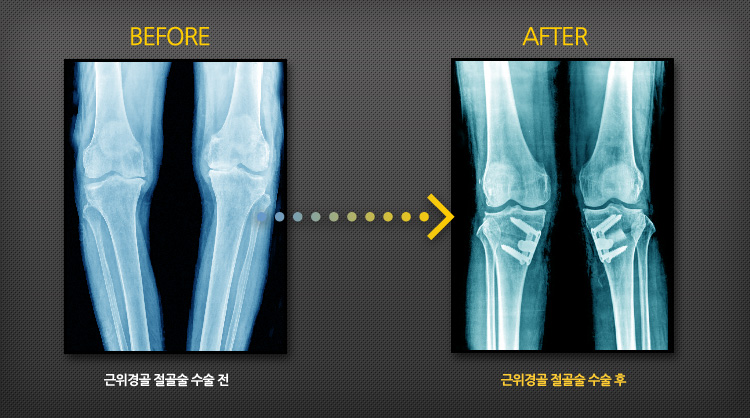

아래의 그림은 근위 경골 절골술은 무릎 아래의 경골 근위에 인위적인 절골을 시행하여 무릎을 'X자형' 다리로 만들어서 무릎관절에 가해지는 힘의 무게를 내측에서 외측으로 옮겨 분산시켜 통증을 완화시키고 자신의 관절로 일상생활이나 근로가 가능하게 원리입니다.